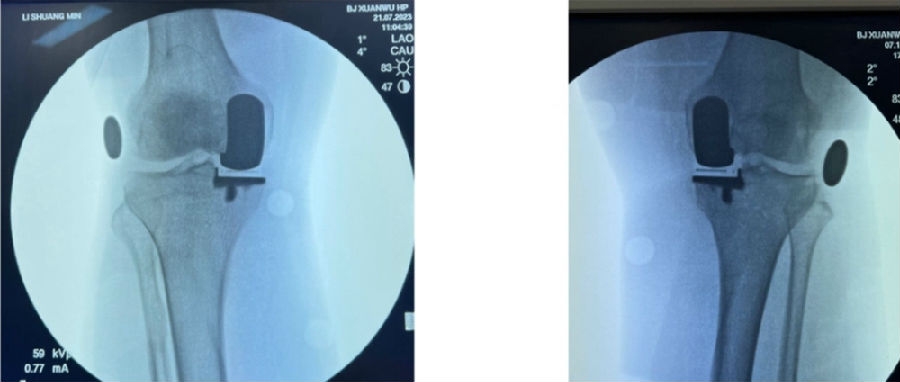

简单总结一下近期的数据,共20例患者的20例膝关节,男5人(25%),女15人(75%),左膝11例(55%),右膝9例(45%)。平均年龄69.8+5.6岁。以±3°作为整个导板设计规划与实际实施的幅度标准。术前规划与术后实际型号没有任何区别,是100%的符合度。

胫骨后倾角有95%的符合度,胫骨内翻角是100%的符合度;胫骨旋转仍然存在一个相对大的差距,但是比传统工具要更好,有70%的病人胫骨内旋角是在范围之内。

股骨在冠状面的角度上也是比较好的表现,股骨内翻角存在95%的符合度,股骨内外旋转角稍差一点,但也达到70%。目前唯一还存在不太满意的地方就是矢状面上股骨假体低头,这个角度偏差度和术前规划差距较大,有50%的准确。

上文回顾之前的一篇文献提到,实际上传统工具和机器人如果按照±2°的话,它只有最高41%的准确度,所以导板能达到目前这样的准确度已经很不错了。但是,后续还有很多需要不断改进探索的地方。